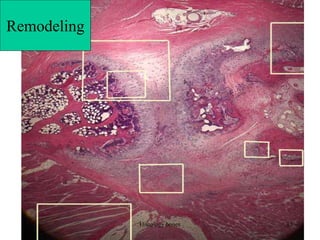

Remodeling

On this image,

the deepest red

color is bone

while pink

represents

either

fibrocartilage

(i.e., collagen

within

cartilage) or

mineralized

cartilage. The

central clearing

represents the

invasion of bone into calcified cartilage. Osteoblasts are laying down

new bone toward the left of the upper boundary of this

cavity. osteoclasts are removing previously-formed bone .